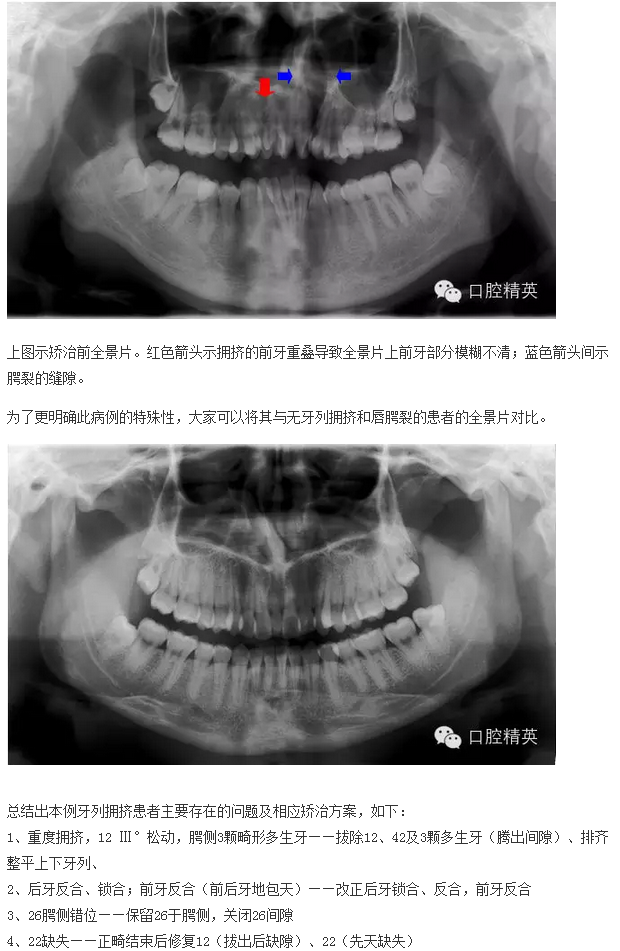

下面來個(gè)圖,震撼一下大家的心靈。